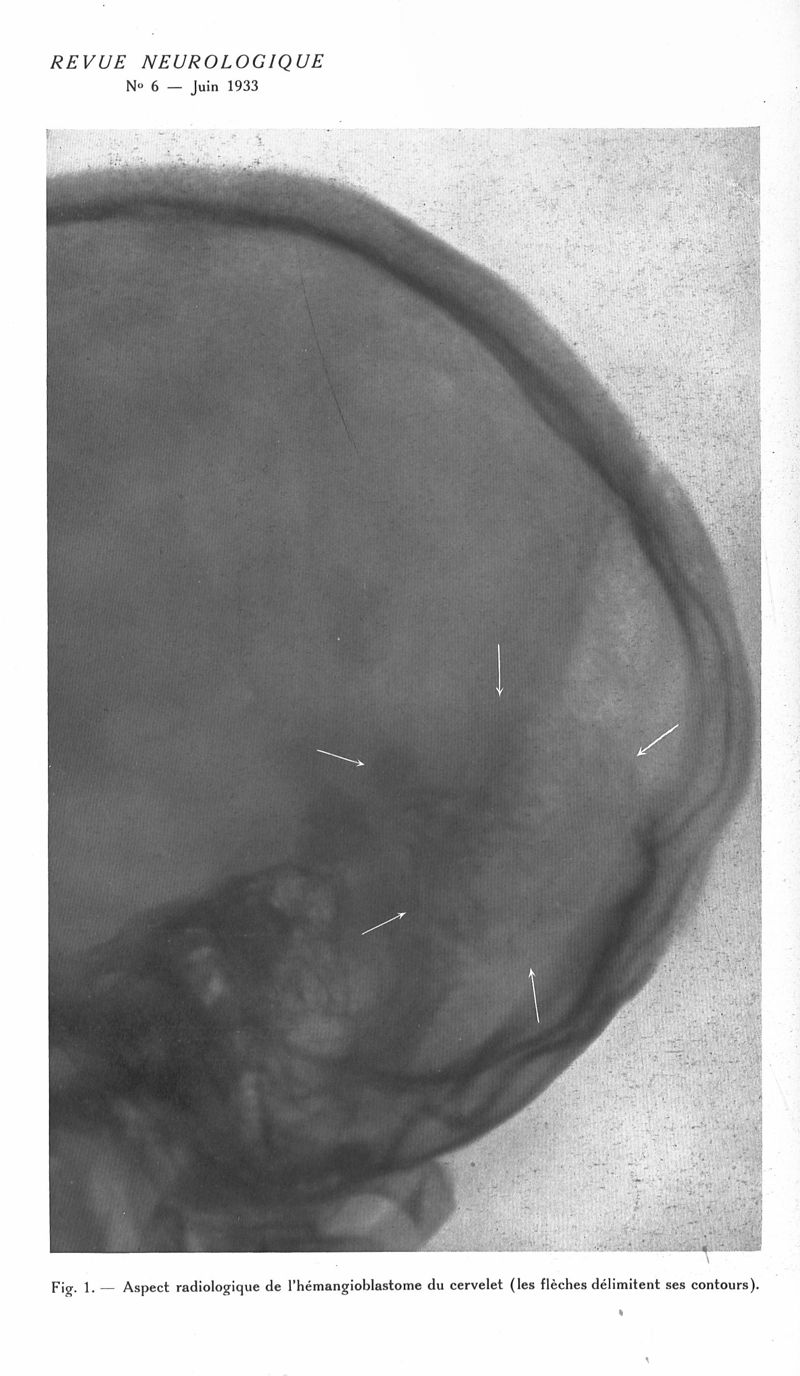

Revue neurologique

1933, vol 1. - Paris : Masson , 1933.